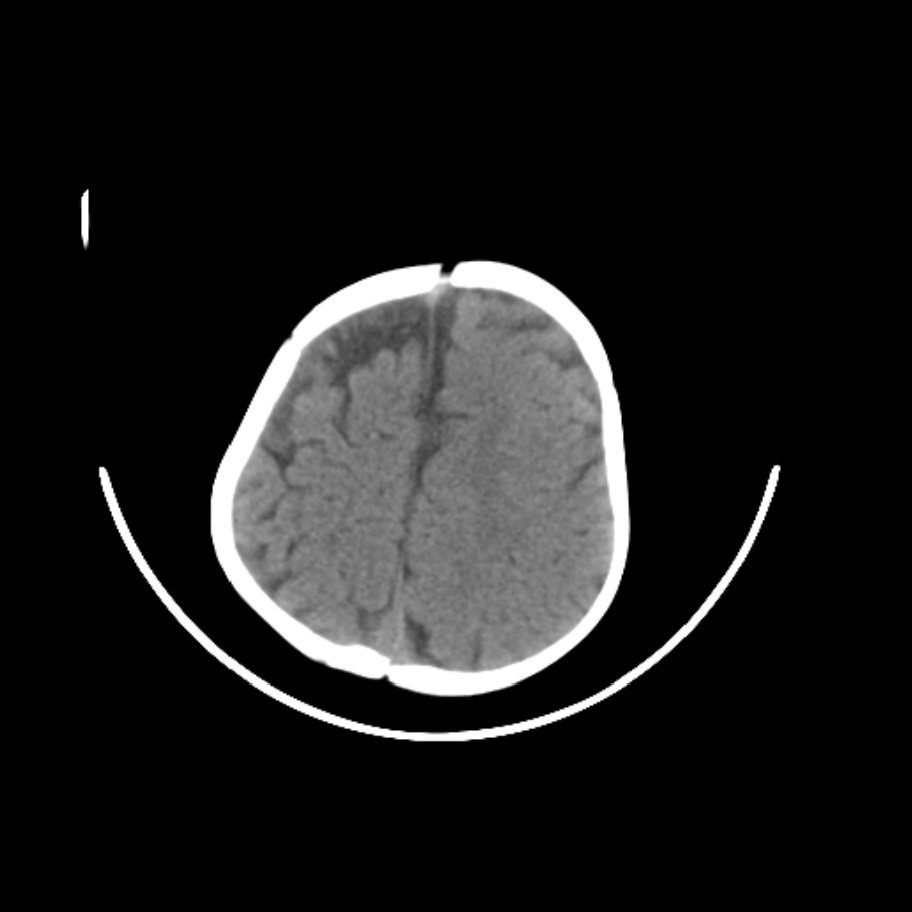

以下是引用随光逐影在2009-4-8 7:51:00的发言:[br]1)透明隔缺如(视-隔发育不良?)。2)右侧脑裂畸形。3)右侧幕上半球脑萎缩。